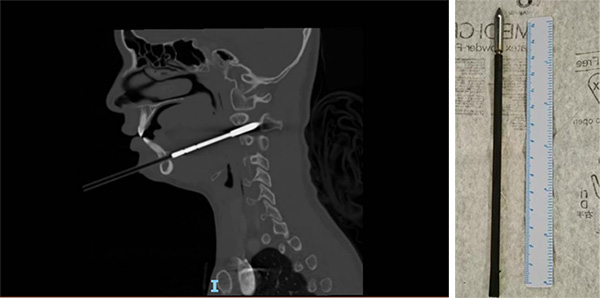

6月2日凌晨,娜娜在父母和教练的陪伴下,紧急抵达北京儿童医院急诊。首诊的急诊内科戴国瑞医师迅速对娜娜的病情进行了全面评估。尽管娜娜的生命体征平稳、神志清楚,肢体活动和感觉也未见异常,但CT影像结果却揭示伤情的复杂性:箭矢穿通了下颌骨和右侧颈2椎体,累及椎管,横突孔内缘骨质可疑受累,且箭头尖段进入椎管长度约12毫米,右侧咽旁间隙受累,局部气道向左侧偏移。

6月2日凌晨2时,娜娜被送入手术室。经验丰富的麻醉科医生在颈部制动、张口受限的复杂情况下,成功完成了气管插管,为这场牵动人心的手术奠定了良好基础。麻醉完成后,耳鼻咽喉头颈外科副主任医师刘悄吟对娜娜的口咽部进行了术前探查,发现多发淤青、水肿和软组织陈旧出血。随后,骨科副主任曹隽主任医师和口腔科副主任医师陈卓合力进行异物拔除。他们首先稳定患儿头部,用大力钳夹住箭杆末端,缓慢拔出。起初阻力较小,但箭头退至下颌骨部位时,阻力明显增加。两位医生凭借精湛的技艺和沉着冷静的心态,在确保患儿生命体征平稳的前提下,加大了拔出力量。最终,深深扎在下颌骨里的箭矢被完整取出!术后再次用喉镜探查,确认无活动性出血。